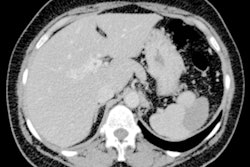

Obtained during a short protocol, this diffusion-weighted image shows a patient with conspicuous liver metastasis. The lesions are marked by arrows. Courtesy of Dr. Thomas Lauenstein. Originally published in the ECR Today newspaper."Hence, a dedicated first-time MRI exam of the liver could encompass more or different sequences than a follow-up exam or a surveillance exam of patients with a high-risk profile," he explained. "If we follow this strategy, examination time can be spared and more exams per time unit could be performed."